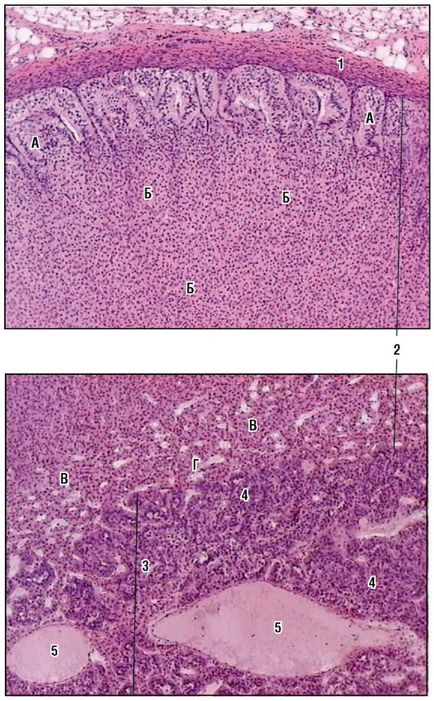

Fig. 170. Glanda parascheită. Vedere generală (colorare cu hematoxilină și eozină): 1 - fragment al lobulei glandei tiroide cu foliculi; 2 - glandă paratiroidă; 3 - fire de paratrocite; 4 - straturi intermediare de țesut conjunctiv; 5 - capilare sanguine

Fig. 171. Nadbochechnik (colorare cu hematoxilină și eozină, creștere mică): 1 - capsulă de țesut conjunctiv; 2 - substanță corticală: zona A - glomerulară; B - zona fasciculului; B - zona ochiurilor de plasă; D - capilare din zona reticulară; 3 - substanța creierului; 4 - celule de cromafină; 5 - vasele de sânge ale măduvei